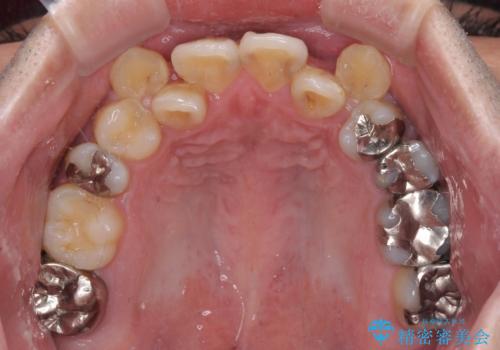

上下ともに八重歯が顕著であったので、上下左右第一小臼歯4本を抜歯し、ワイヤー装置にて矯正治療を行うこととしました。

デコボコが強いことが原因で歯間部に汚れが溜まりやすい状態でしたが、矯正前にできる限り汚れが少なくなるようにブラッシングなどの指導を行い、口腔状態が改善された後にワイヤー装置を装着することとしました。